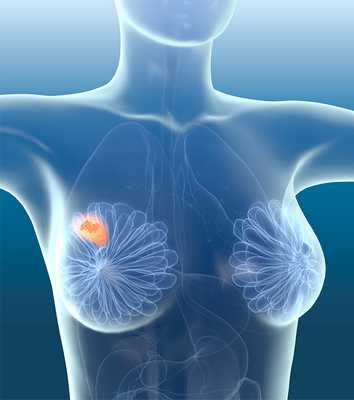

По распространенности рак молочной железы (РМЖ) занимает первое место среди онкологических заболеваний. Он поражает ежегодно 1 млн. 600 тыс. женщин в мире и свыше 66 тыс. в Российской Федерации.

Рак молочной железы – самая распространенная онкологическая патология у женщин, а в общей структуре злокачественных заболеваний – занимает второе место после рака легких. Более того, заболевание обладает еще и высоким уровнем летальности. Мужчины хоть и болеют на порядок реже, но рак протекает у них более агрессивно, к тому же они долгое время откладывают обращение к специалисту, увеличивая риски неблагоприятного исхода.

Карцинома молочных желез – это синоним словосочетания «рак груди», злокачественная опухоль, которая развивается из клеток молочной железы. Ежегодно заболевание диагностируется у порядка 65 тысяч российских пациенток, средний возраст больных чуть старше 61 года. Существуют разные типы карцином молочных желез, обычно они проявляются в виде уплотнений в груди, изменения ее размеров, внешнего вида кожи. В ранней диагностике заболевания помогает маммография. Если рак груди удалось выявить на ранних стадиях, то шансы полностью удалить опухоль и добиться ремиссии весьма высоки.